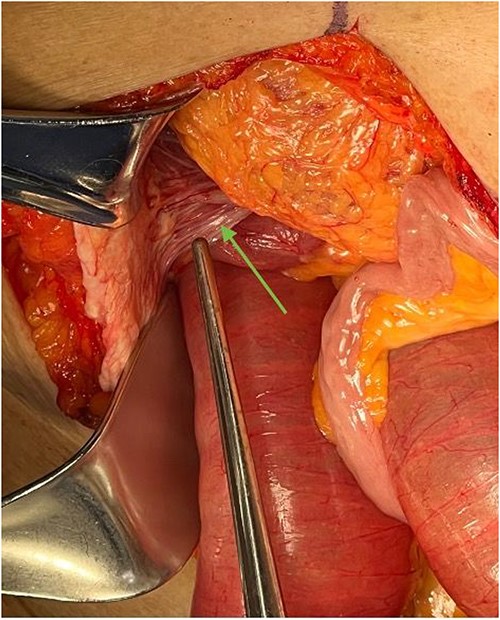

To attempt decompression, a nasogastric tube was placed and collected 1400 cc of fecal material immediately. The decision was made to take the patient for exploratory laparotomy based on suspected midgut volvulus with associated acute small bowel obstruction. Intraoperatively, the patient was found to have Ladd’s bands and the bowel was found to be twisted around a narrow mesenteric base with the cecum in the right upper quadrant (Fig. 2).

Ladd’s bands are noted in the right upper quadrant during exploratory laparotomy, indicated by an arrow. In this case, these bands adhere the cecum to the abdominal wall.